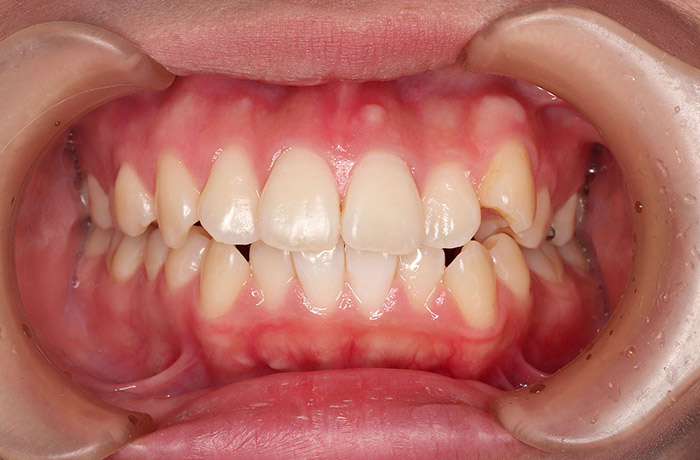

K様

治療前

年齢 27歳

性別 女性

治療名称 マウスピース型カスタムメイド矯正歯科装置(インビザライン)・コンプリヘンシブパッケージ(フルパッケージ)

総額治療費用 770,000円(税込10%) 金額備考 精密検査料・診断料 33,000円(税込10%)

治療期間 1年11か月 通院頻度など 40日ごと

1枚につき10日装着を指示しました。

治療内容

患者の症状 上顎前歯の前突、八重歯

治療方法 上下左右の第一小臼歯抜歯で、マウスピース型カスタムメイド矯正歯科装置による矯正

治療結果 上顎前歯の前突、八重歯が改善されました。

歯並びをより良くするために追加でアライナーを発注しました。

リスク/副作用 決められた時間装着する必要があります。